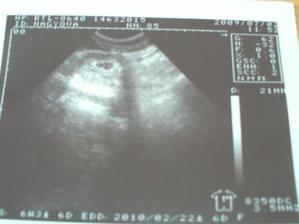

triple test - negativní

21.9.2009 prvni pohyby. koplo tatinka do ucha.🙂

29.9.2009 - genetika - vše v pořádku